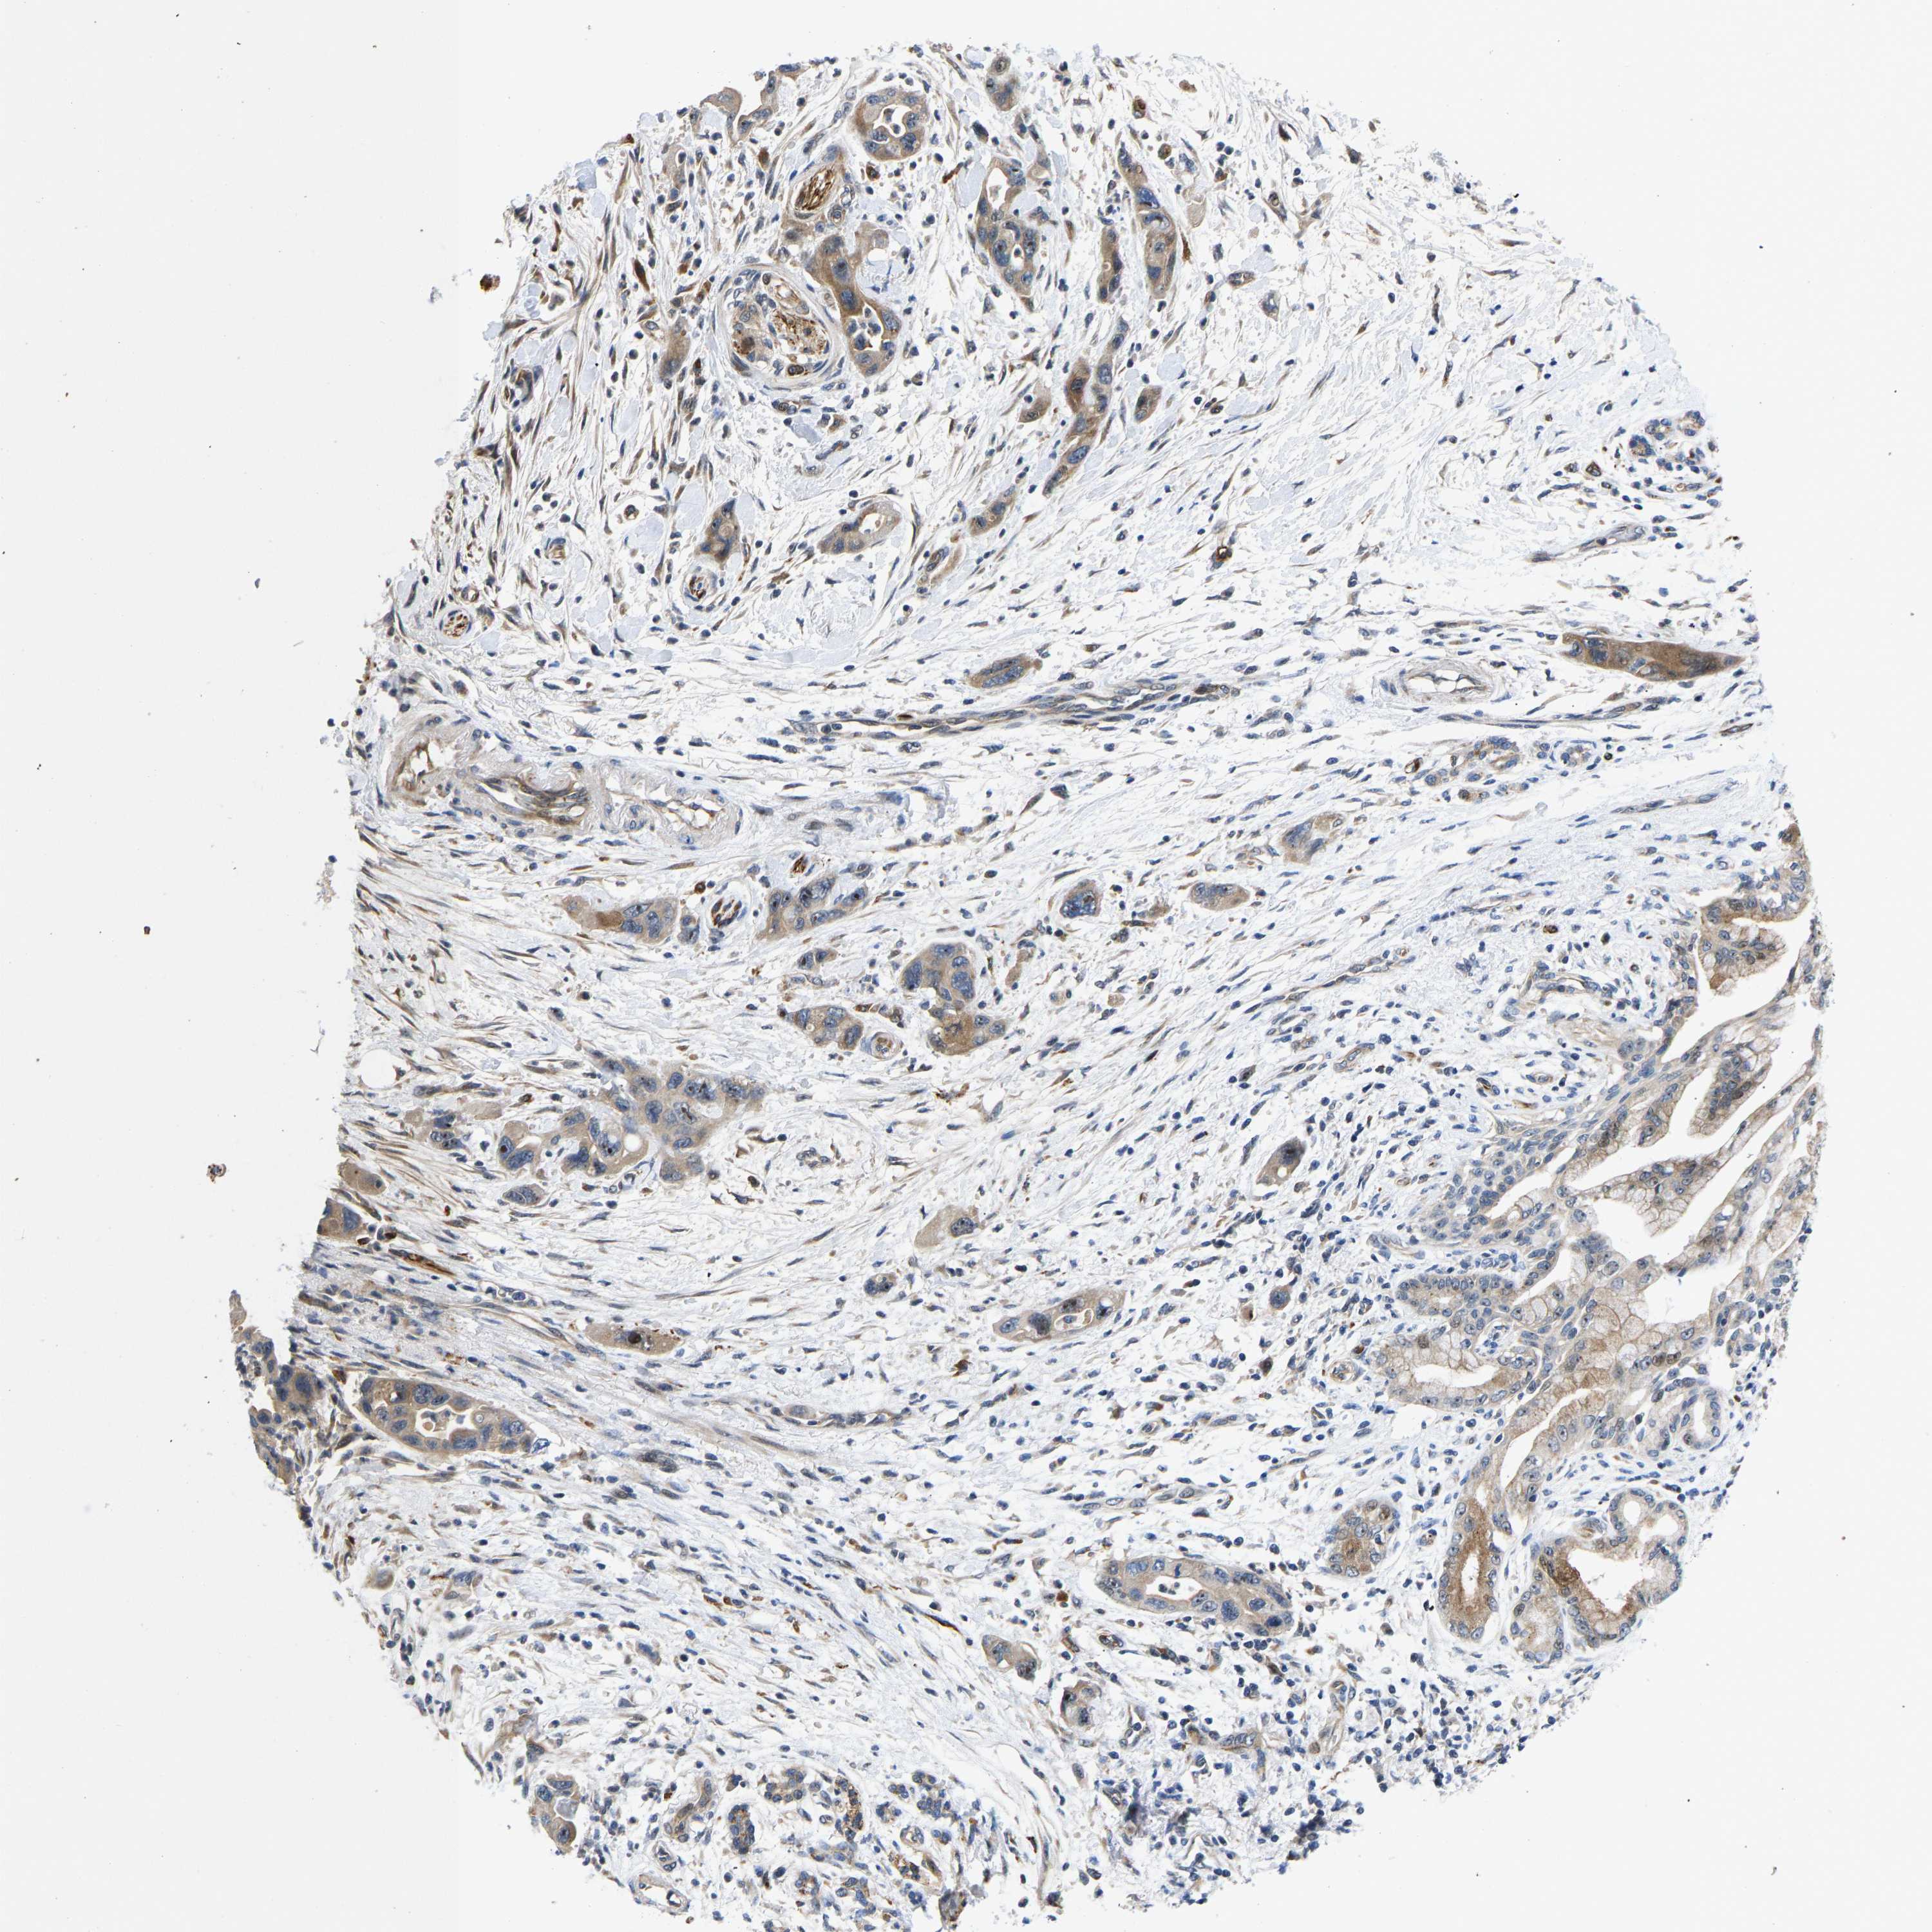

PANCREATIC CANCER - Protein expressioni

A mouse-over function shows sample information and annotation data. Click on an image to view it in a full screen mode. Samples can be filtered based on level of antibody staining by selecting one or several of the following categories: high, medium, low and not detected. The assay and annotation is described here.

Note that samples used for immunohistochemistry by the Human Protein Atlas do not correspond to samples in the TCGA dataset.

Antibody stainingi

Antibody staining in the annotated cell types in the current human tissue is reported as not detected, low, medium, or high, based on conventional immunohistochemistry profiling in selected tissues. This score is based on the combination of the staining intensity and fraction of stained cells.

Each image is clickable and will lead to virtual microscopy that enables deeper exploration of all samples and also displays staining intensity scores, fraction scores and subcellular localization as well as patient and tissue information for each sample.

Antibody HPA013816

Antibody HPA015622

Staining

High

Medium

Low

Not detected

Intensity

Strong

Moderate

Weak

Negative

Quantity

>75%

75%-25%

<25%

None

Location

Nuclear

Cytoplasmic/membranous

Cytoplasmic/membranous,nuclear

Adenocarcinoma, NOS